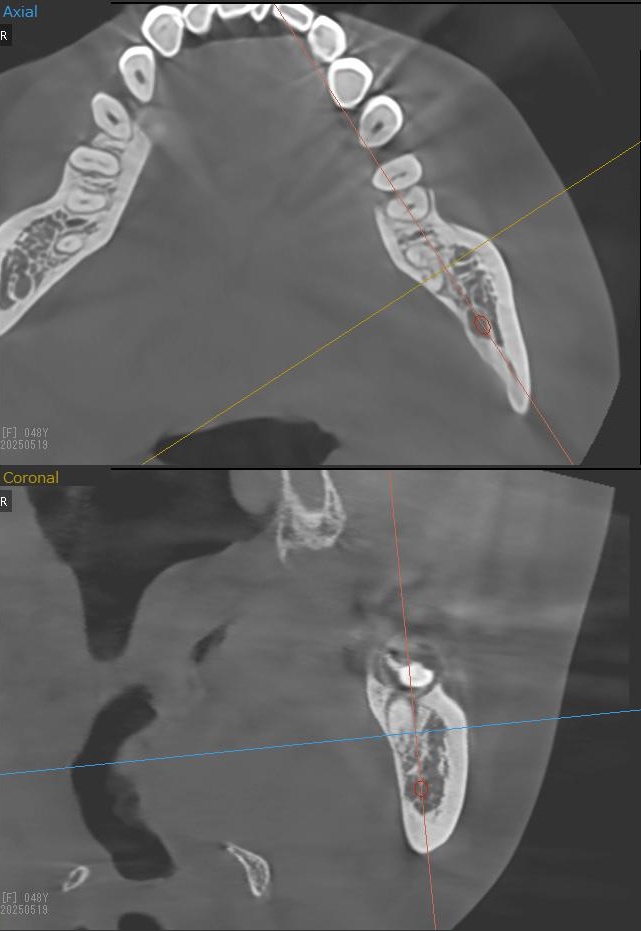

さらに、下顎の親知らずは下歯槽神経に非常に近いところに生えている場合もあるため、CTも撮影し詳しい解析を行います。

親知らずが生えている位置が、神経に近い、あるいは神経に当たっている場合は、大きな病院に紹介する場合もあります。

親知らずの根っこは下歯槽神経から近い距離にありますが、抜歯は可能との診断でした。